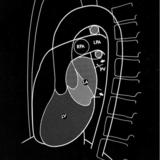

Left chambers PA

Date: 03/02/2006

Views: 2667